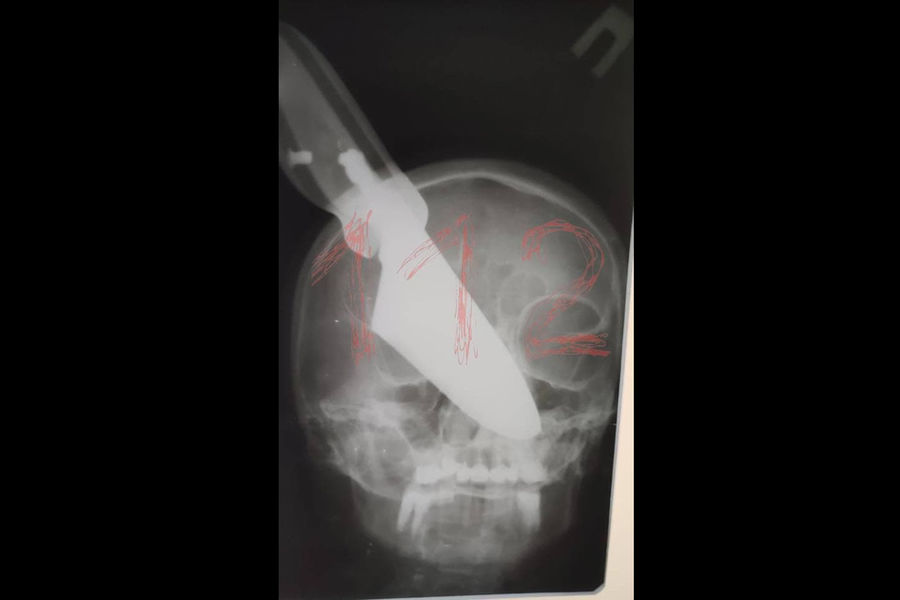

На Кубани в ходе семейной ссоры мужчина воткнул нож в лицо своей супруги

В городе Апшеронске Краснодарского края в ходе семейной ссоры мужчина воткнул нож в лицо своей супруги — женщина осталась жива, сообщается на сайте Следственного комитета по Кубани.

Инцидент произошел вечером 19 ноября, когда 64-летний мужчина и 60-летняя женщина распивали спиртные напитки, находясь у себя дома. В ходе ссоры мужчина схватил нож и ударил свою жену ножом в область носа.

Клинок застрял в лице женщины, которая сумела отбиться от мужа и выбежать на улицу, где позвала на помощь.

«Местные жители вызвали на место бригаду скорой медицинской помощи и правоохранителей. Пострадавшая была доставлена в больницу, где ей продолжают оказывать медицинскую помощь», — указано в сообщении.

Мужчина был задержан, ему предъявлено обвинение по ч. 3 статьи 30 и ч. 1 статьи 105 УК РФ в покушении на убийство.